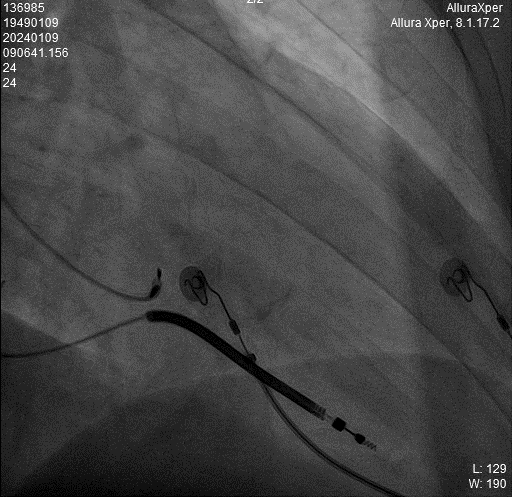

术中HIS电极影像

LBB影像位置

术中影像 HIS-HISD-消融靶点